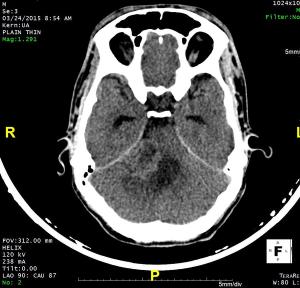

75-year-old male presented with left-sided weakness, headache, and altered sensorium.